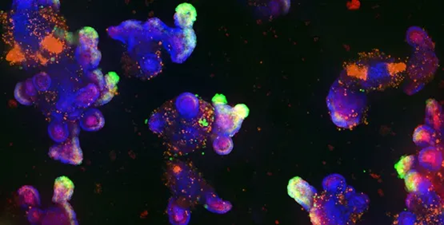

Colorectal cancer (CRC) organoids

Image Credit: Molecular Devices UK Ltd

Ten CRC organoid (PDO) lines have been developed using adult stem cells from colorectal cancer patient biopsy tissue.

Colorectal cancer (CRC) organoids

Image Credit: Molecular Devices UK Ltd

Patient-derived colorectal cancer organoids, also known as colorectal cancer PDOs or CRC organoids, are multicellular miniature versions of the three-dimensional tumor that are cultivated in a laboratory. It has been demonstrated that they exhibit drug responses comparable to those of their derived organoids and maintain the in vivo features of the original tumor. This presents revolutionary opportunities for drug discovery and medical research.